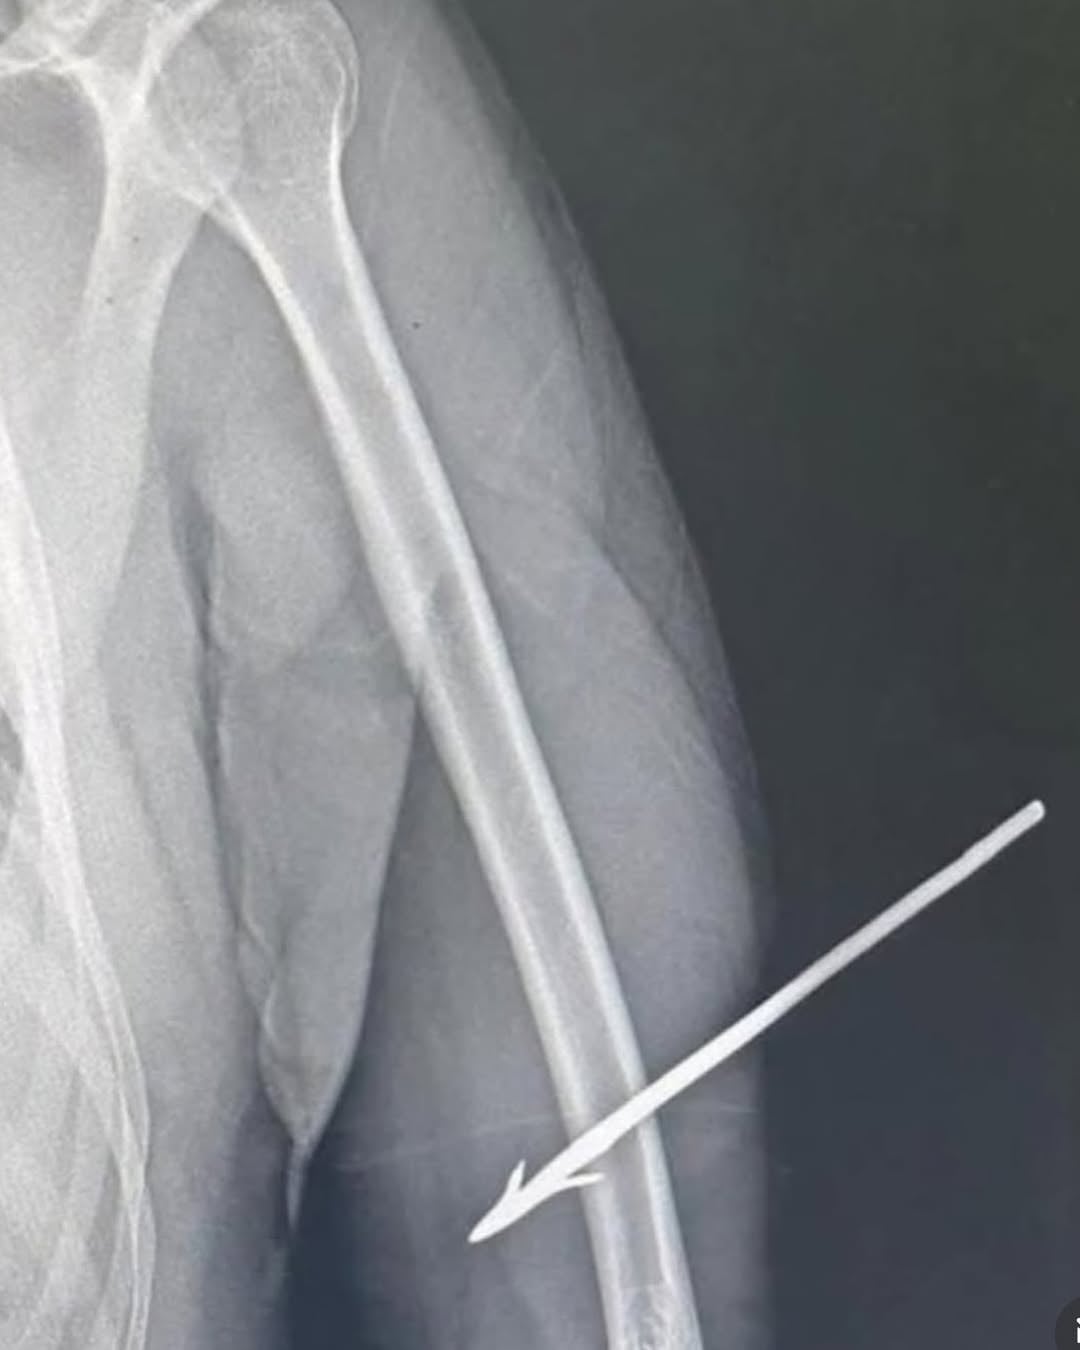

At the hospital, imaging tests revealed that the arrow went through the arm and was embedded in the bone. Despite the severity, the medical team found that the officer was in a stable condition and had no signs of shock. He was taken to the surgical center to remove the object and remains hospitalized under observation and medical care.